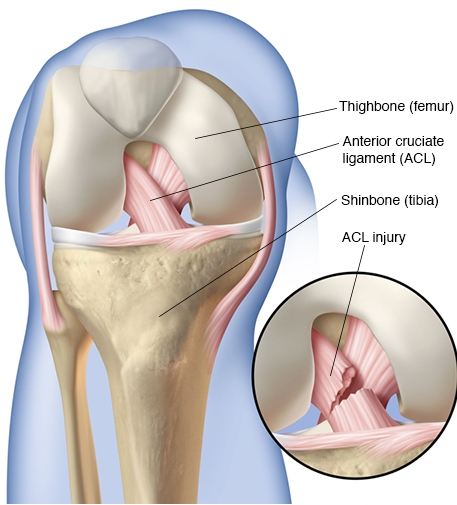

ACL Injury

The ACL (Anterior Cruciate Ligament) is one of the four major ligaments critical to the stability of the knee joint. Its primary purpose is to restrain forward motion of the shinbone. An ACL injury occurs when this ligament is torn.